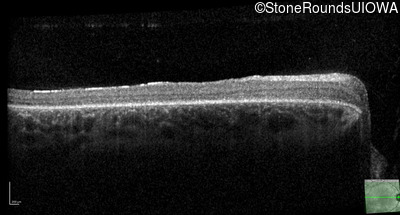

Optical Coherence Tomography - Right - 20/100 -1 sc

Exemplar / OCT Stack

OCT Stack